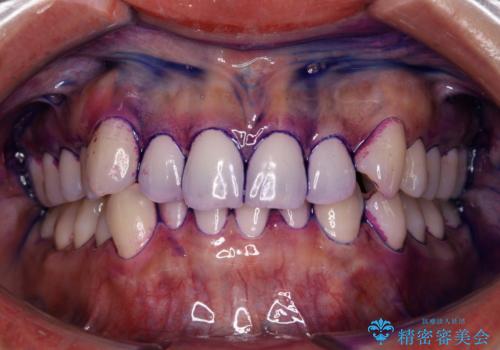

染め出しをしてエアフローで綺麗にクリーニング

染め出し液を使ってプラークを染め出すことにより、普段の歯みがきで磨き残している場所を目で確かめることができます。